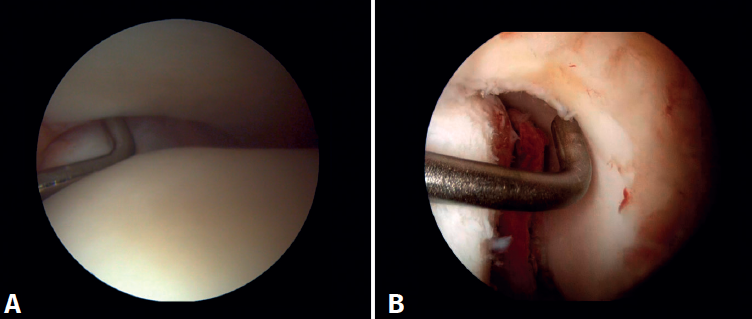

Arthroscopic evaluation of the syndesmosis

From the anteromedial portal we can directly visualize the distal fibers of the ATFL. Disinsertion of these fibers does not always result in instability of the syndesmosis, but it does require us to check it. In our experience, we prefer assessment of the coronal plane of the syndesmosis. We introduce the arthroscope into the tibiotalar joint directing the camera cranially. In this way we have a direct view of the distal tibiofibular joint. We then assess stability by attempting to insert the palpation probe into the joint. If it is possible to do so, we classify the syndesmosis injury as unstable (Figure 6A).

Arthroscopic evaluation of the deltoid ligament

There are multiple methods for assessing instability of the medial complex; using the anterior ankle portals it is possible to assess the stability of the deltoid ligament in its main plane of action, corresponding to the coronal plane. Chun et al.(20) described instability when it is possible to introduce an arthroscopic palpation probe into the medial tibiotalar space (Figure 6B). Vega et al.(21) reported that, in the majority of injuries, the most anterior portion of the deltoid ligament is detached from the medial malleolus, while its proximal insertions remain intact. In this situation, the arthroscopic palpation probe can be inserted between the medial wall of the internal malleolus and the deep fibers of the deltoid ligament.